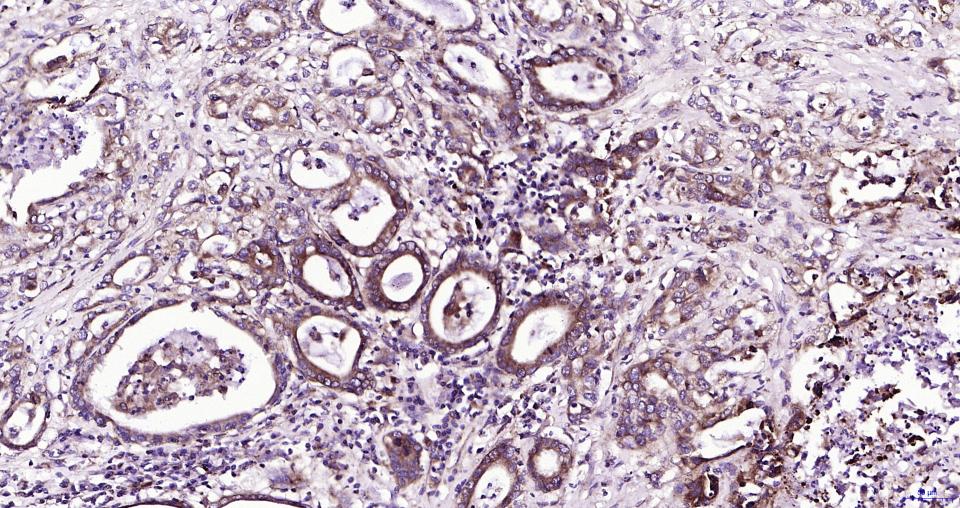

Paraformaldehyde-fixed, paraffin embedded Human Pancreatic Cancer; Antigen retrieval by boiling in sodium citrate buffer (pH6.0) for 15 min; Antibody incubation with Parkin Monoclonal Antibody, Unconjugated(bsm-61396R) at 1:200 overnight at 4°C, followed by conjugation to the SP Kit (Rabbit, SP-0023)and DAB (C-0010) staining.

Paraformaldehyde-fixed, paraffin embedded Human Kidney; Antigen retrieval by boiling in sodium citrate buffer (pH6.0) for 15 min; Antibody incubation with Parkin Monoclonal Antibody, Unconjugated(bsm-61396R) at 1:200 overnight at 4°C, followed by conjugation to the SP Kit (Rabbit, SP-0023)and DAB (C-0010) staining.

Paraformaldehyde-fixed, paraffin embedded Rat Kidney; Antigen retrieval by boiling in sodium citrate buffer (pH6.0) for 15 min; Antibody incubation with Parkin Monoclonal Antibody, Unconjugated(bsm-61396R) at 1:200 overnight at 4°C, followed by conjugation to the SP Kit (Rabbit, SP-0023)and DAB (C-0010) staining.

Paraformaldehyde-fixed, paraffin embedded Human Colon; Antigen retrieval by boiling in sodium citrate buffer (pH6.0) for 15 min; Antibody incubation with Parkin Monoclonal Antibody, Unconjugated(bsm-61396R) at 1:200 overnight at 4°C, followed by conjugation to the SP Kit (Rabbit, SP-0023)and DAB (C-0010) staining.